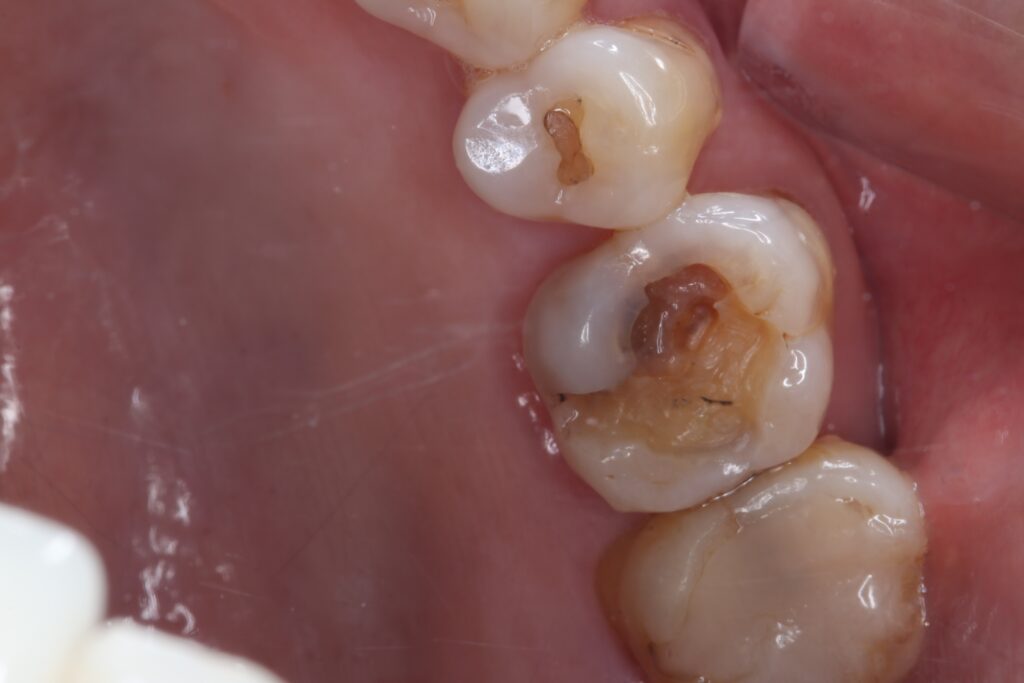

セラミック症例③

年齢30代女性

治療期間1ヶ月

治療内容セラミックインレー

治療箇所右下4番

治療費用100,000円